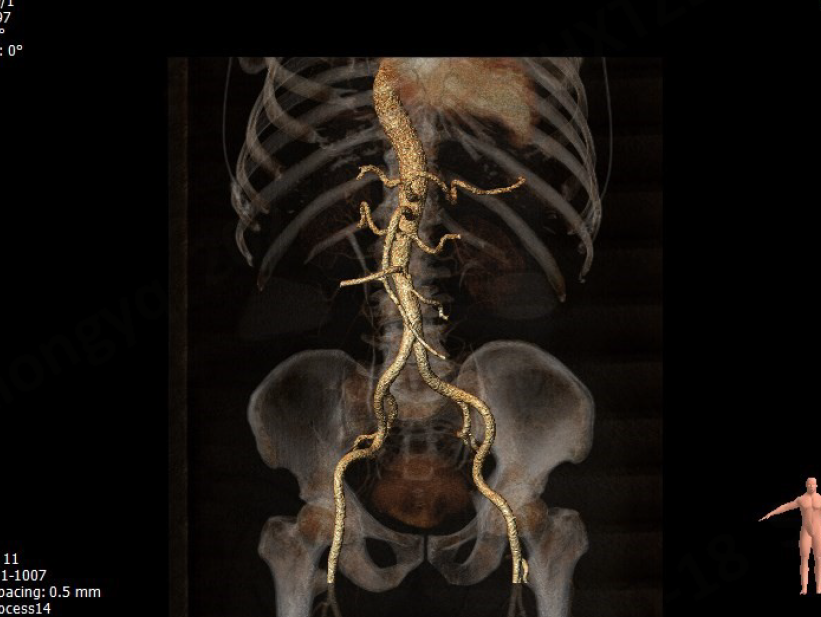

入路情况

股动脉入路轻度迂曲

• 股动脉入路条件尚可,轻度迂曲,无明显钙化团块。